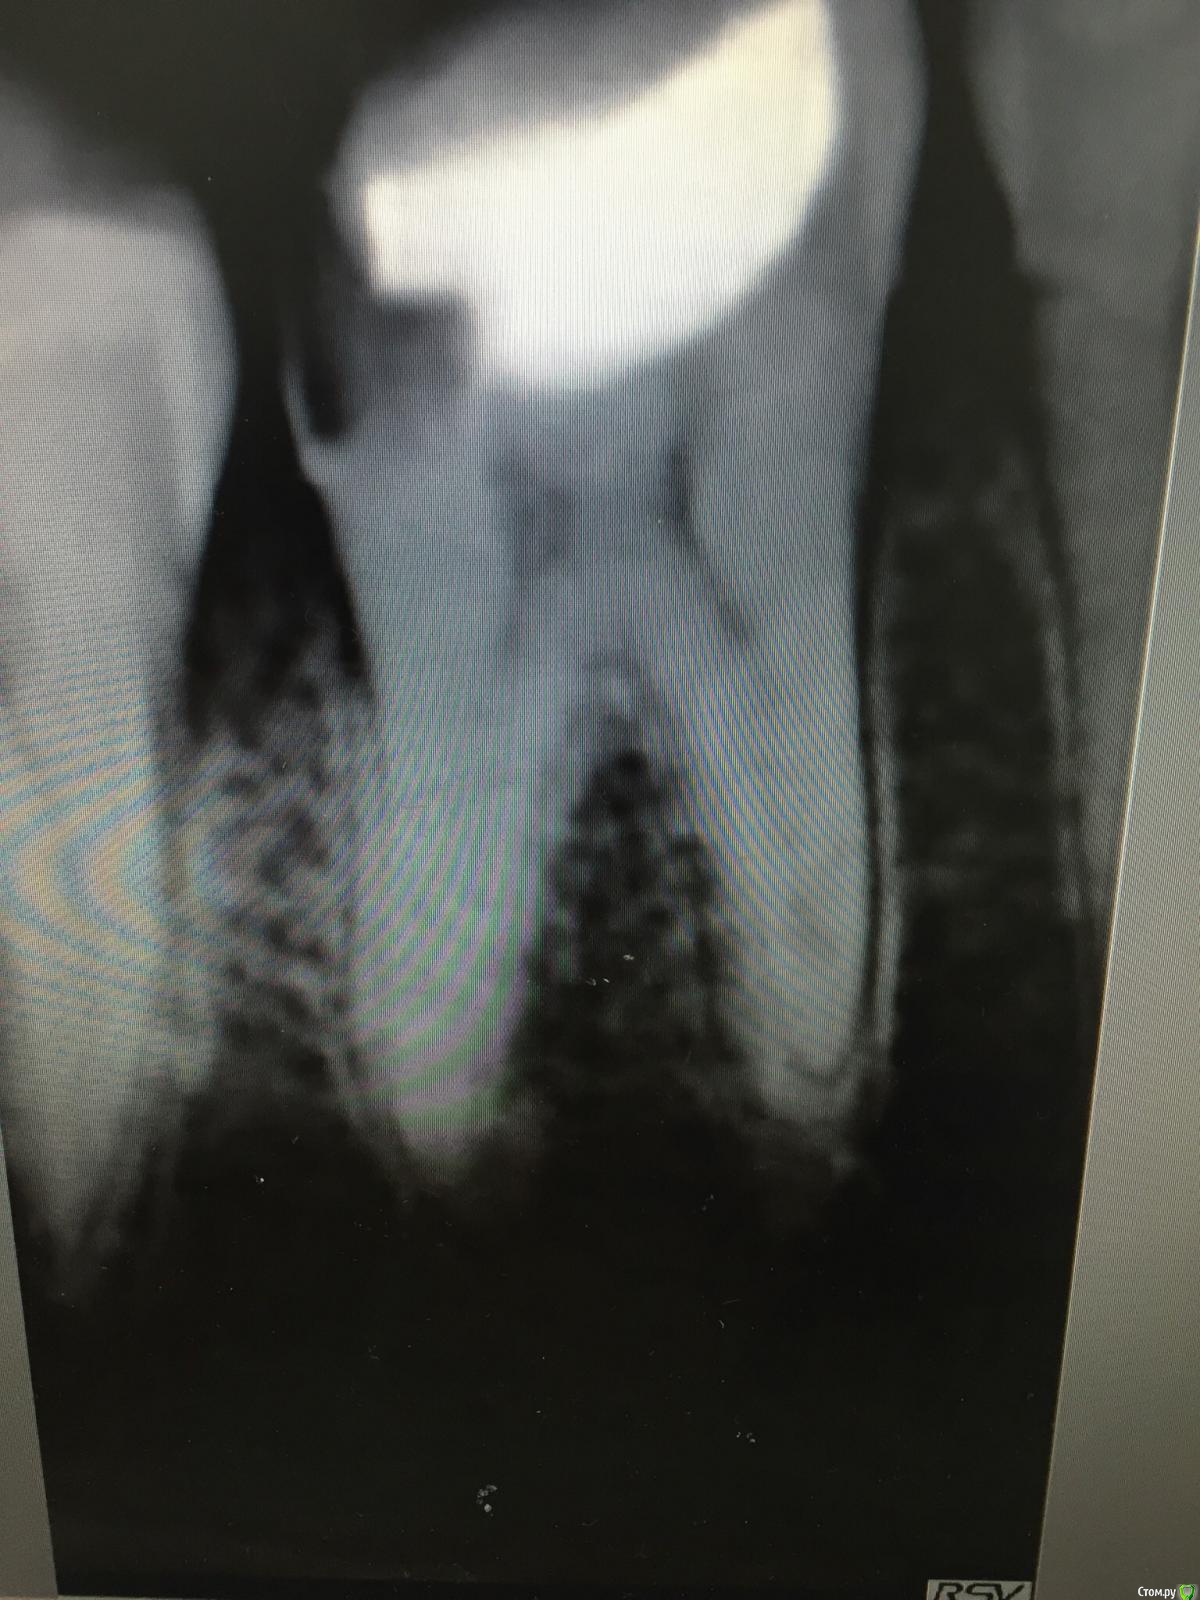

Ирина Игоревна Опубликовано 13 декабря, 2017 Поделиться Опубликовано 13 декабря, 2017 пациентка обратилась с жалобой на боль при попадании пищи. Зуб пролечен по глубокому кариесу, краевой прилегание нарушено. Пломбу убрала, все кариозные ткани тоже, пульпа вскрылась. Пульпа кровила долго, пришлось депульпировать. Каналы сильно облитерированы. Дистальные с горем попалась прошла, в медиальных дохожу до середины, дальше как ни бьюсь 08, 10, не могу нащупать продолжение канала. Устьевую часть предварительно расширила, вроде не заступенила, но такое ощущение что каналы там пропадают) В полости попеременно эдта с хлоркой. Файлы пробывала подгибать, в надежде хоть где то зацепиться, но безуспешно. Пока оставила ходить с каласептом. Пациентке все рассказала, предложила продолжение лечения в другой клинике под микроскопом ( я работаю в бино), но она категорически отказывается . Остальные шестерки у неё зарезорцинены, говорит такая же ситуация была. Коллеги, посоветуйте что ещё попробовать Ссылка на комментарий

Kolchanov Опубликовано 13 декабря, 2017 Поделиться Опубликовано 13 декабря, 2017 Они там, конечно. Облитерация-то с коронковой пульпы начинается, просто хитрый изгиб, или блокада дентиклем каким. Если не идет, витальное эндо, нет возможности безопасно расшириться, чтобы увидеть, то какие еще варианты? Ссылка на комментарий

dentikl Опубликовано 13 декабря, 2017 Поделиться Опубликовано 13 декабря, 2017 может попробовать камеру мезиально дораскрыть,может кт посмотреть . Ссылка на комментарий

Ирина Игоревна Опубликовано 14 декабря, 2017 Автор Поделиться Опубликовано 14 декабря, 2017 может попробовать камеру мезиально дораскрыть,может кт посмотреть .Устья я нашла, думаю раскрытие камеры ещё больше приведёт лишь к истончению стенок. Я не могу пройти в медиальных дальше верхней трети каналов. На доп расходы пациентка не готова. Я предложила ей продолжить лечение в другой клинике с микроскопом ( отказ), пломбирование на пройденную длину и наблюдение. В случае отрицательной симптоматики прибегнуть к хирургическому методу ( резекция или удаление). Она сказала что это все сложно и проще удалить. Поэтому в след визит после кальция попробую ещё нащупать каналы, если будет всё так же глухо, то, по совету коллег, запломбирую как есть, и восстановлю композитом с перекрытием бугров. Просто думаю внутренний голос будет грызть, когда пац потом придёт с симптоматичным периодонтитом ( не думаю что она будет приходить на проф осмотры), и скажет что болит зуб который у вас лечила. Как правило осадок остаётся , несмотря на все объяснения и предупреждения Ссылка на комментарий